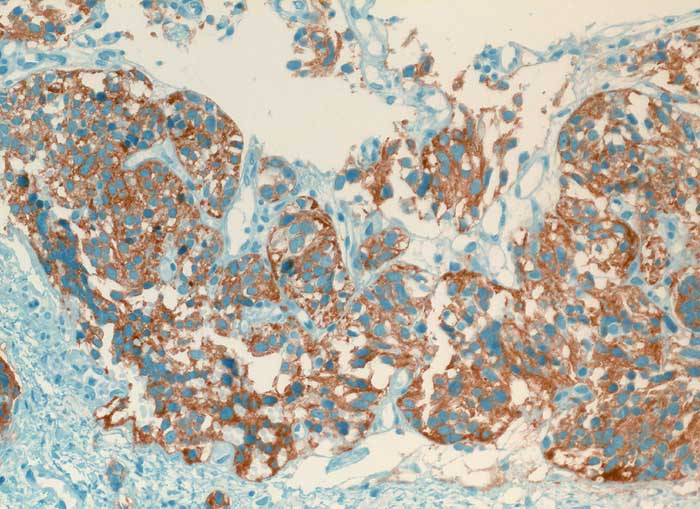

pit/ Typisches Karzinoid der Lunge

Typisches Karzinoid der Lunge

Die Diagnose hoch differenzierter neuroendokriner Tumoren ist schwierig, da ihre Oberfläche meist von Bronchialschleimhaut oder Bronchialepithel bedeckt ist und sie deswegen kaum Zellen abschilfern. Ausserdem sind die Atypien sehr diskret. Die Zellkerne sind rundlich bis oval, glatt begrenzt, fein granuliert und haben grosse Ähnlichkeit mit den Kernen von Flimmerzellen. Ohne Kenntnisse des klinischen Befundes sind Karzinoidzellen deshalb kaum von Basal- und Flimmerzellen zu unterscheiden. Der Zytoplasmasaum ist schmal und zerfällt leicht. Solche nackt liegenden Kerne können mit einem Lymphom verwechselt werden. Das typische Karzinoid hat eine sehr gute Prognose, kann aber in seltenen Fällen metastasieren. Die Unterscheidung von typischem und atypischem Karzinoid erfolgt am histologischen Schnitt durch Nachweis von Nekrosen und mehr als 3 bis 10 Mitosen pro HPF bei letzterem.